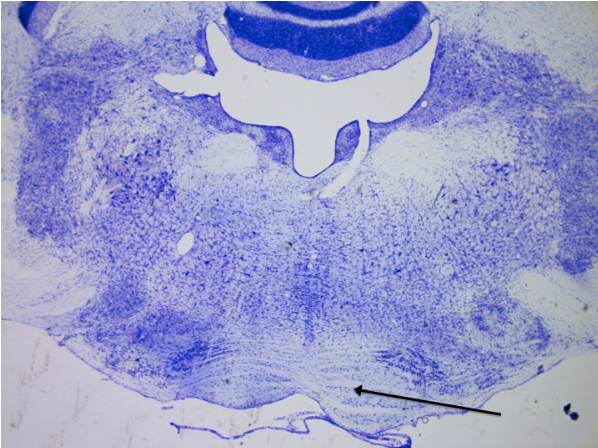

1

New cards

Nucleus accumbens

knowt flashcard image